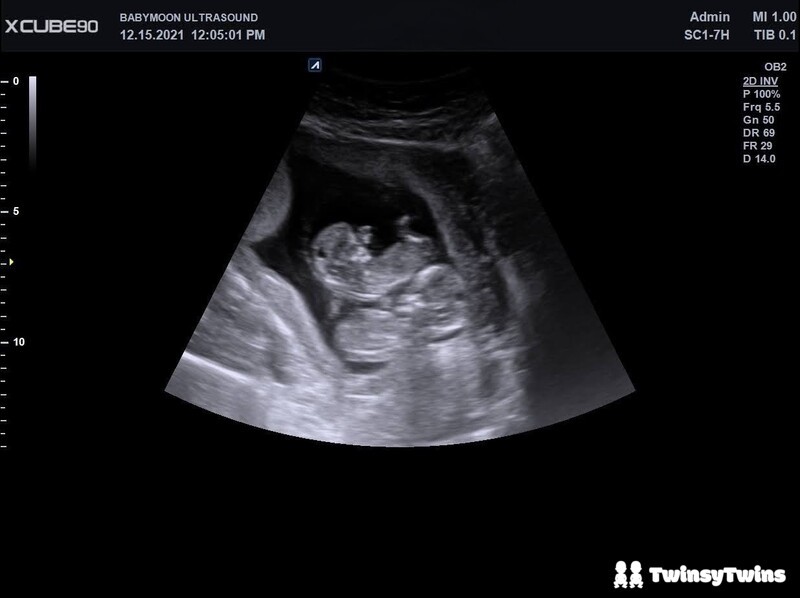

Tracking movement in utero for multiple babies is tricky, if not nearly impossible.

When you've got twins in there, if you feel a kick, flutter, or roll, you have to pay attention to where you felt the movement and the angle of the striking appendage, then think back to your last ultrasound and where everybody was nestled up, and try to determine which baby you felt.

With twins, it's almost impossible to know, without a doubt, which baby you're feeling kick at any given moment. You can give your best guess, but even then, you could get them mixed up.

Try to time how long it takes you to get to 10 movements for each of your babies. When they're cramped closely in tight quarters, this can be tricky. It might be less boggling if you know how they're currently positioned and can focus on one area (and, therefore, hopefully distinguish one baby).

Beyond the placenta(s), you've, of course, got two babies crammed into cramped living quarters, so it's pretty hard to know with absolute certainty who you feel, even if you THINK you know because they roll around and can move position so often while they're in utero.

On a day I had a fetal assessment appointment, I was sure I felt Baby B kicking me in a specific spot, but when the technician did the ultrasound, the sonogram showed it was actually Baby A I felt.

They'd changed up their positions since my appointment a few days prior, so what I'd thought was Baby B's hand was actually Baby A's leg.